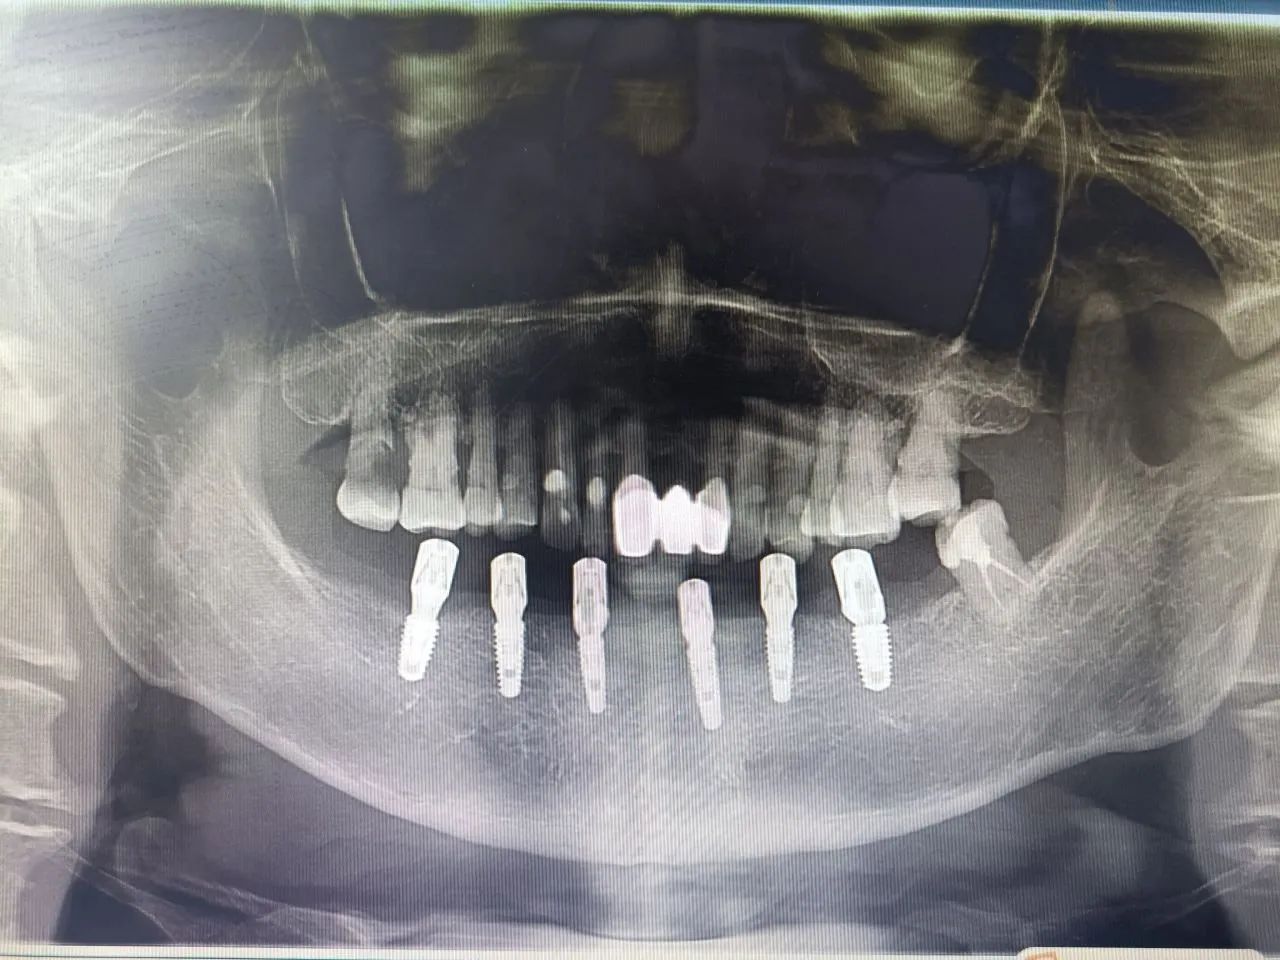

-下半口种植+即刻修复后-

-下半口种植+即刻修复后-